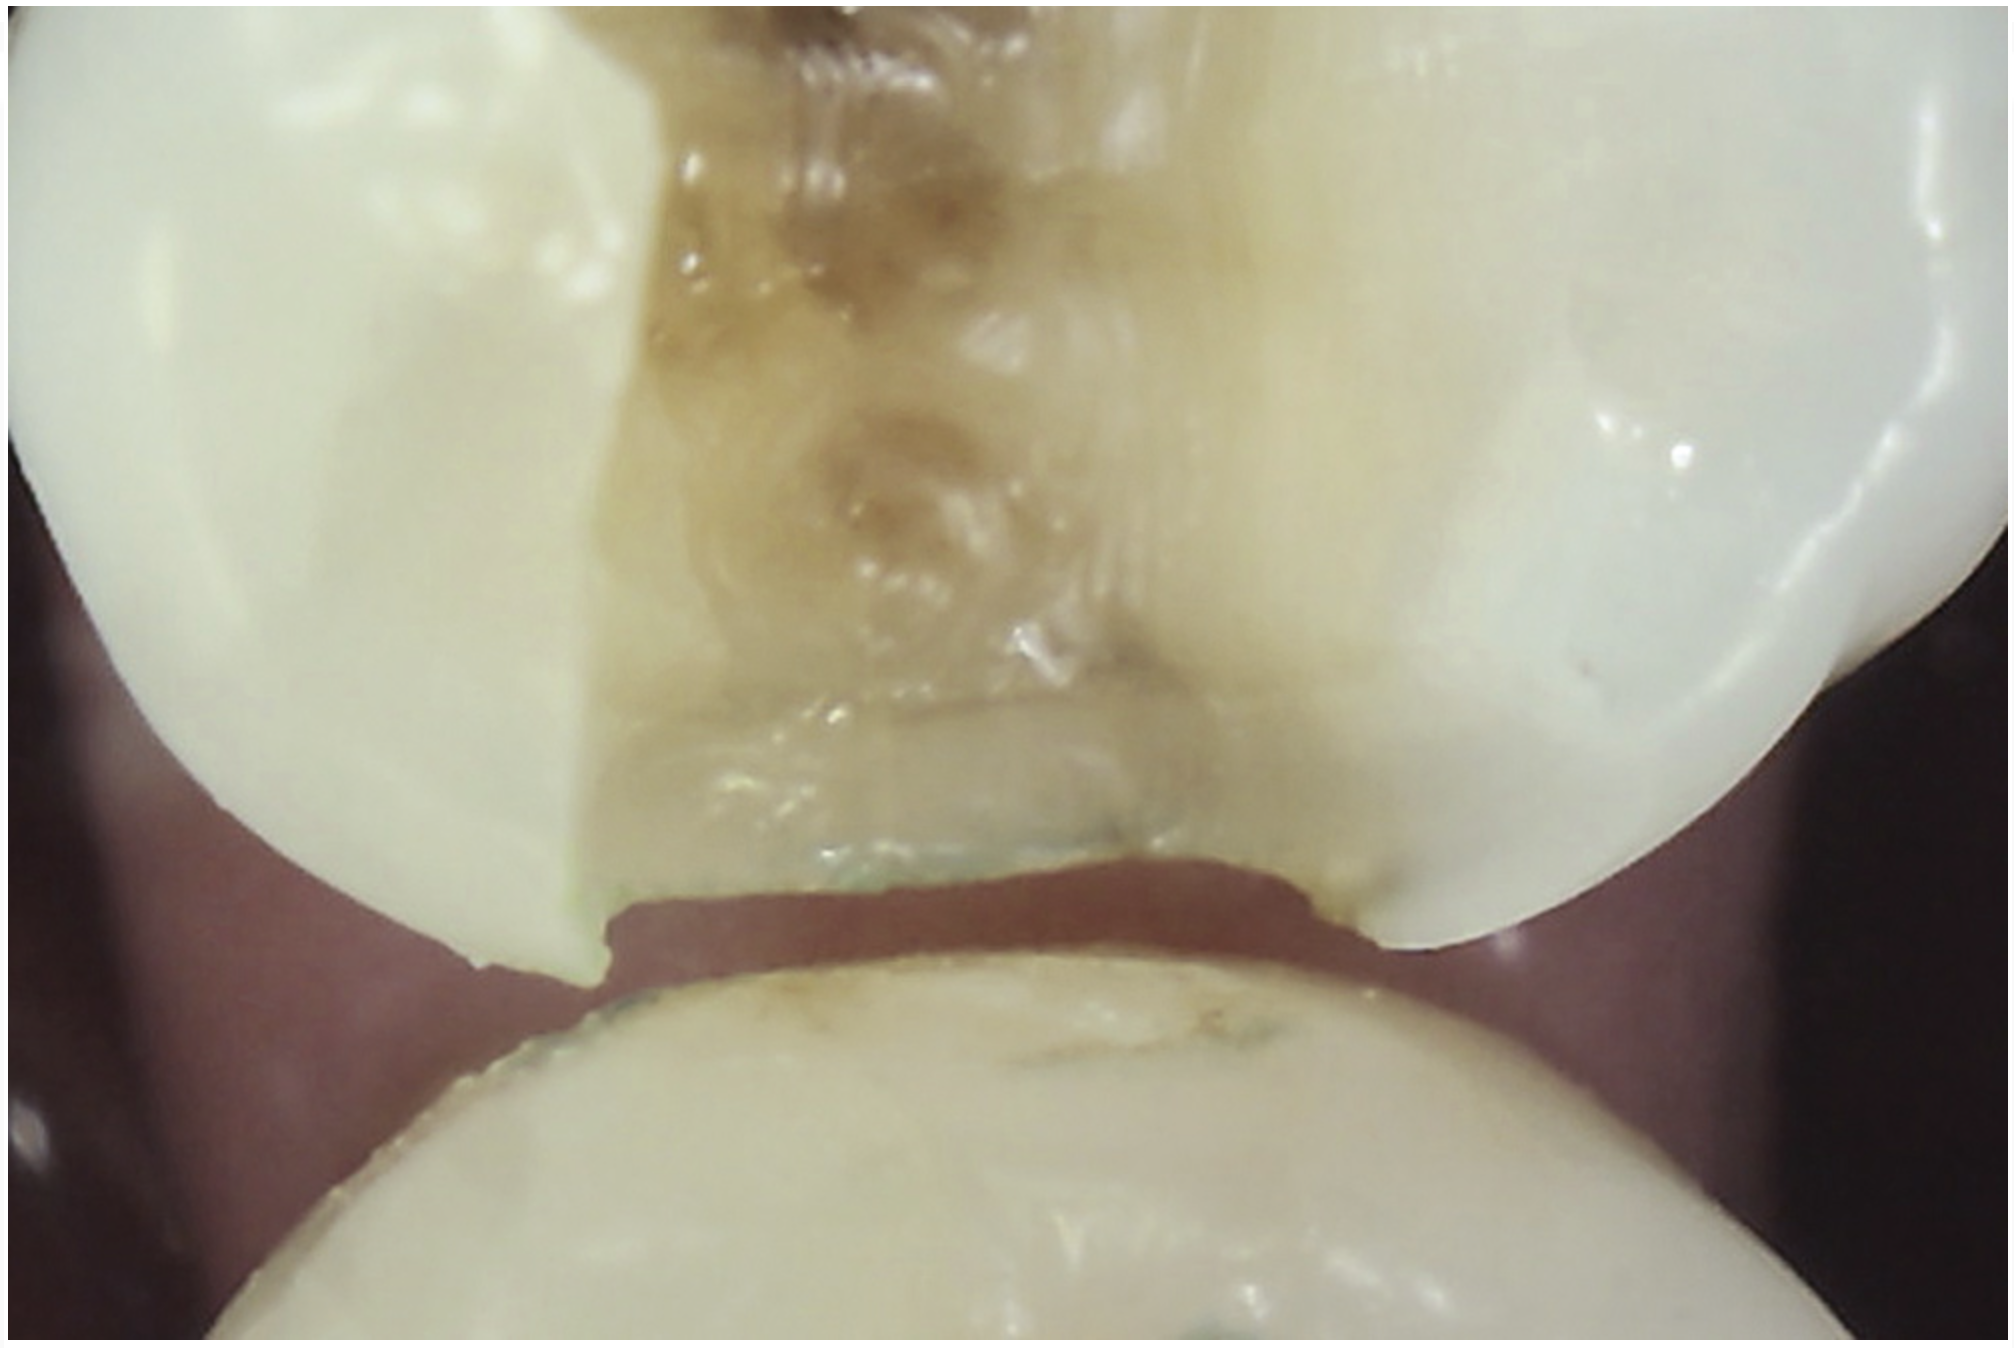

Whenever asymptomatic enamel cracks extend into dentin and cannot be eliminated by minimally invasive fissurotomy without causing additional damage to the tooth and underlying structures, protection is recommended to minimize their propagation (Figure 10 and Figure 11).3,14 Occlusal coverage restorations have demonstrated greater overall success in the treatment of symptomatic cracks by immobilizing the cracked segments that move on loading, with better prognosis seen when more conservative restorations are used.27,28 Although this might still be controversial, from a biomechanical perspective these principles can conceptually apply to the treatment of asymptomatic dentin cracks. Occlusal coverage restorations have been recommended to protect asymptomatic teeth with existing dentin cracks from further cracking (Figure 12).2,3,9,29

Fig 10. Stained asymptomatic enamel marginal ridge crack (arrows) of a maxillary right first molar extending to the existing restoration (mesio-occlusal view).

Figure 10

Fig 11. Exploratory fissurotomy and methylene blue dye staining revealing an underlying deep dentin crack in tooth shown in Fig 10.

Figure 11